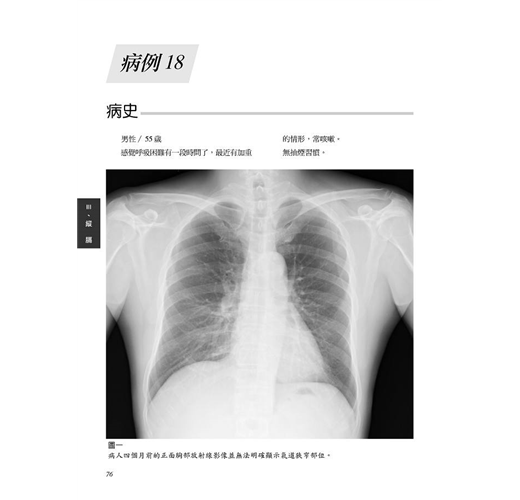

病例18 甲狀腺乳突癌合併氣管侵犯 76

(Tracheal tumor-thyroid papillary carcinoma with trachea invasion)